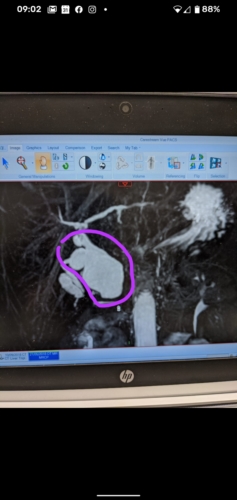

Ive attached a picture of my cyst. If anyone has images would also like to see 😃